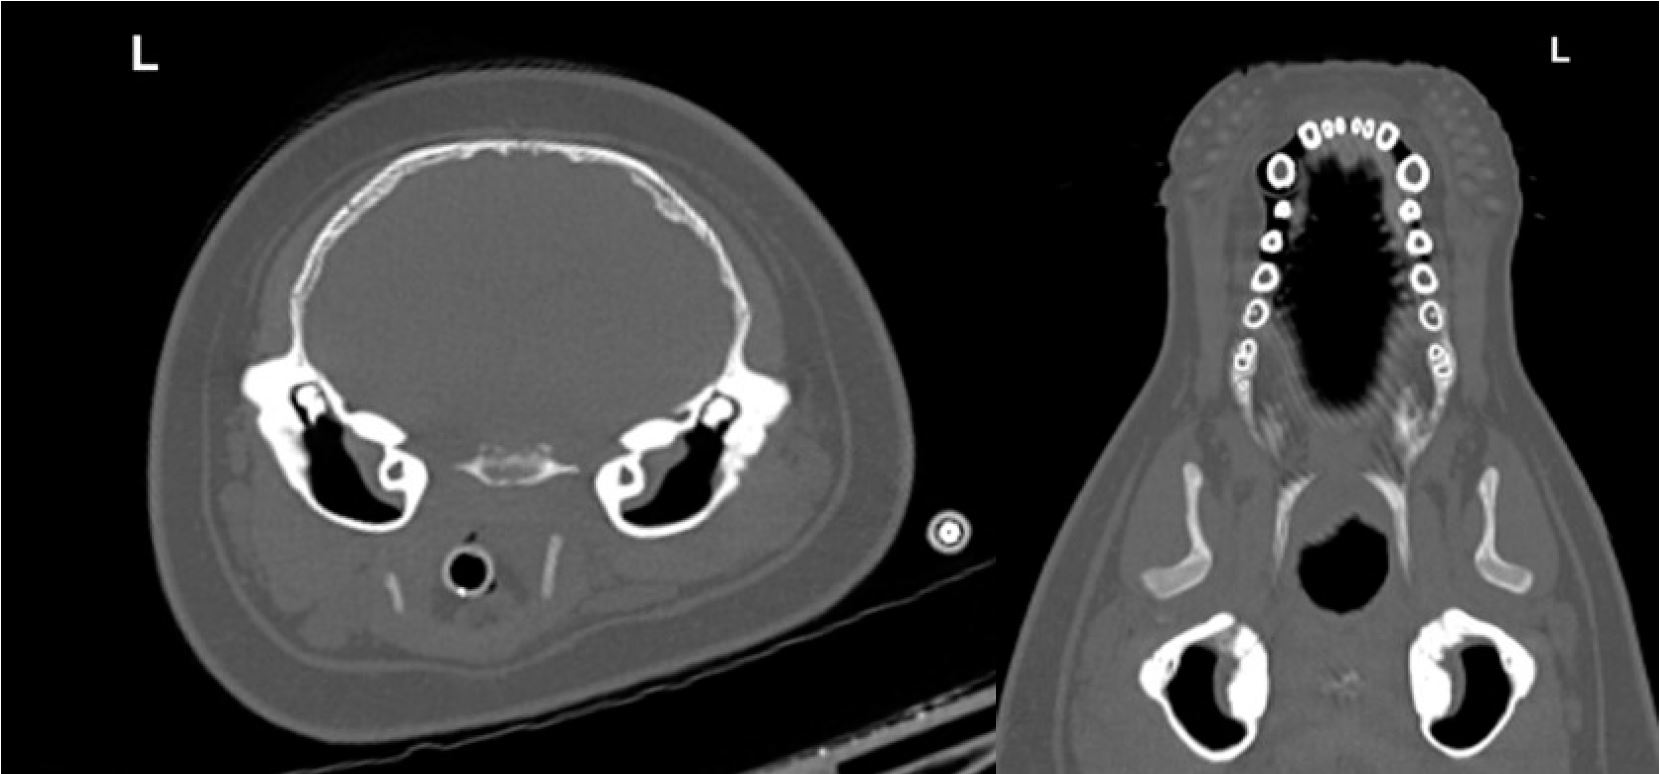

Печінковий синус та велика селезінка

На комп’ютерній томографії всіх пацієнтів у паренхімі печінки виявлено велику порожнину, яка вбирає рідину. Цей висновок узгоджується з тонкостінним печінковим синусом, структурою, утвореною розширенням печінкових вен, що впадають у задню порожнисту вену. Тюлені також показали велику селезінку порівняно з собаками. Поєднання великої порожнини печінки та великої селезінки також зустрічається в інших пірнаючих ссавців.

Шийний венозний синус

Постконтрастне дослідження Вінсента показало ефектне венозне сплетення в шийному відділі (мал. 8). Ці судини вбудовані в коричневу жирову тканину5. Кровотік через сплетення посилюється під час пірнання. Його точна функція невідома, але було припущено, що сплетення допомагає знизити температуру тіла, можливо, уповільнюючи метаболізм і зберігаючи кисень6.

Малюнок 7: Аксіальні зображення живота Вінсента до і після контрастування показують велику заповнену рідиною порожнину в печінці, що відповідає печінковому синусу (GB — жовчний міхур).

Малюнок 8: Аксіальні зображення шиї Вінсента до і після контрастування показують венозне сплетення.

Малюнок 9: корональний вид показує чітке поглинання контрасту обома нирками. Характерною є багатолопатева структура, яка виглядає як «білі крапки».